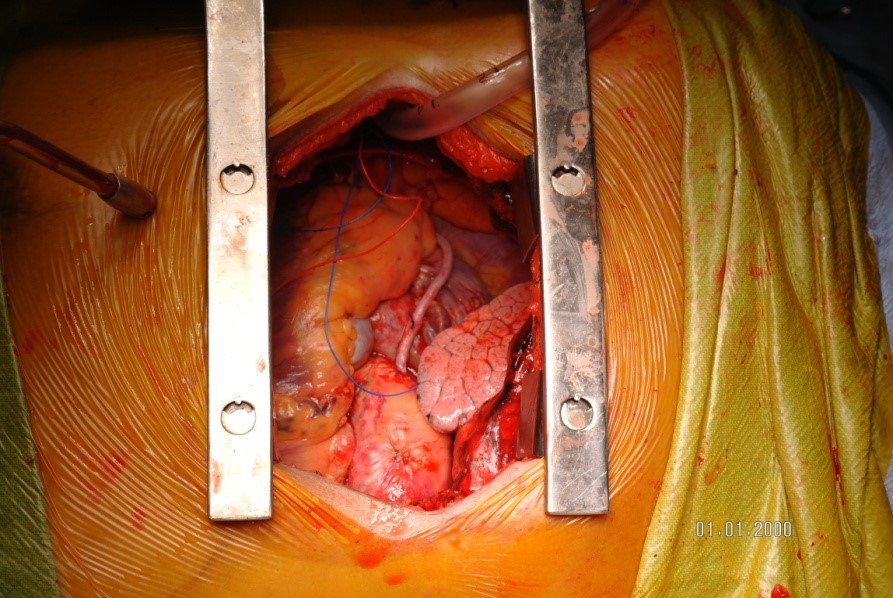

The patient was taken to surgery for a right atrial myxoma excision. A median sternotomy and pericardiotomy was done. Surprisingly, upon examination an 8 x 5 cm mass was found outside the right atrium (RA), adherent to part of the RA wall and encircling the RCA. The patient was placed on cardiopulmonary bypass with cardioplegic arrest. The mass was carefully dissected and removed en-bloc along with part of the RCA. The ostium of the RCA was sutured and buried. Pericardium was harvested and used to reconstruct the RA wall. The tricuspid valve was examined and checked for valve regurgitation. A saphenous vein graft was harvested from the left leg. The distal anastomosis to the RCA and the proximal anastomosis to the aorta were done with 7-0 and 6-0 prolene sutures, respectively. Distal flow was confirmed with a Doppler probe. The patient was gradually weaned off of cardiopulmonary bypass and the chest was closed in layers.